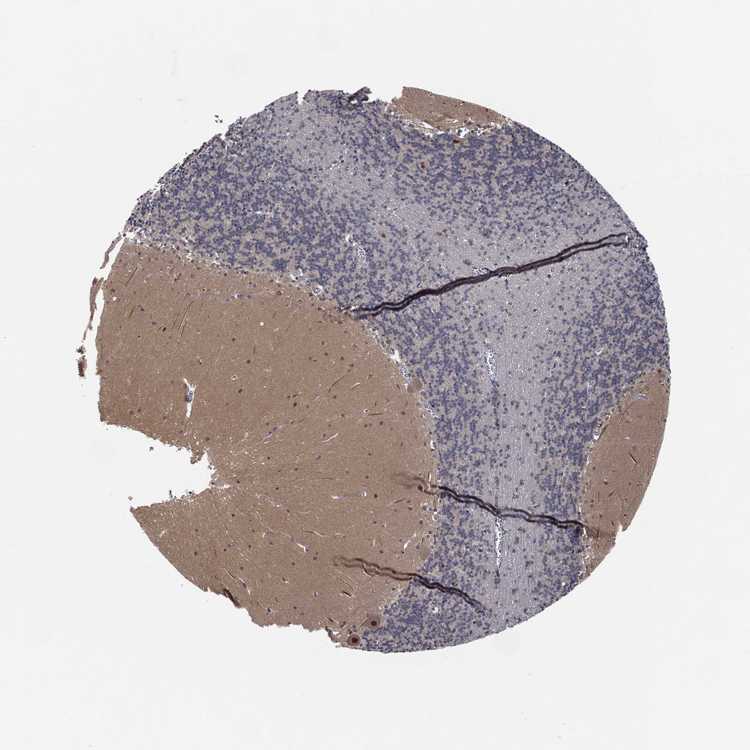

CEREBELLUM - Antibody stainingi

Antibody staining in the annotated cell types in the current human tissue is reported as not detected, low, medium, or high, based on conventional immunohistochemistry profiling in selected tissues. This score is based on the combination of the staining intensity and fraction of stained cells.

Each image is clickable and will lead to virtual microscopy that enables deeper exploration of all samples and also displays staining intensity scores, fraction scores and subcellular localization as well as patient and tissue information for each sample.

Antibody HPA028539Antibody HPA061094

Purkinje cells MediumMedium

Cells in granular layer LowNot detected

Cells in molecular layer Not detectedLow